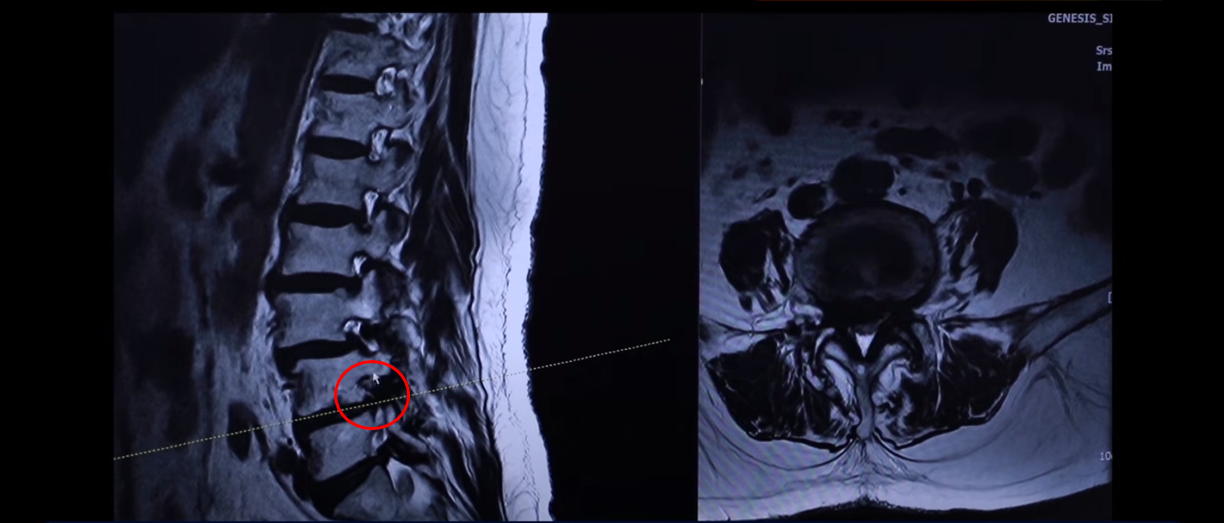

이분 근육 상태를 이 MRI에서 볼 수 있는 부분이 있습니다. 특히 이 하부 요추 5번 1번에서 보시면 이게 허리를 펴주는 기립근이라는 근육입니다.

이 근육을 보시면 왼쪽 화면에 정상적인 기립근의 모양을 비교 해보시면 이런 데가 정상적인 근육은 까맣게 보여야 됩니다. 그게 정상적인 근육인데 보시면 하얗게 변해 있죠. 이게 지방으로 변해버린 겁니다.

이렇게 지방으로 변해버리면 힘을 못 씁니다. 그래서 허리를 펴기도 어렵고 허리를 지탱하기도 어려운 거죠.